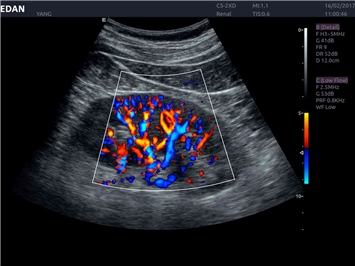

EDAN Acclarix LX4 представляет собой инновационную ультразвуковую систему, построенную на усовершенствованной платформе Acclarix. Сочетание высокого качества визуализации с интеллектуальным рабочим процессом делает эту систему оптимальным выбором для клиник, ценящих эффективность и экономичность.

Трехмерная реконструкция ЦДК:

Да

Энергетический допплер:

Color 3D: